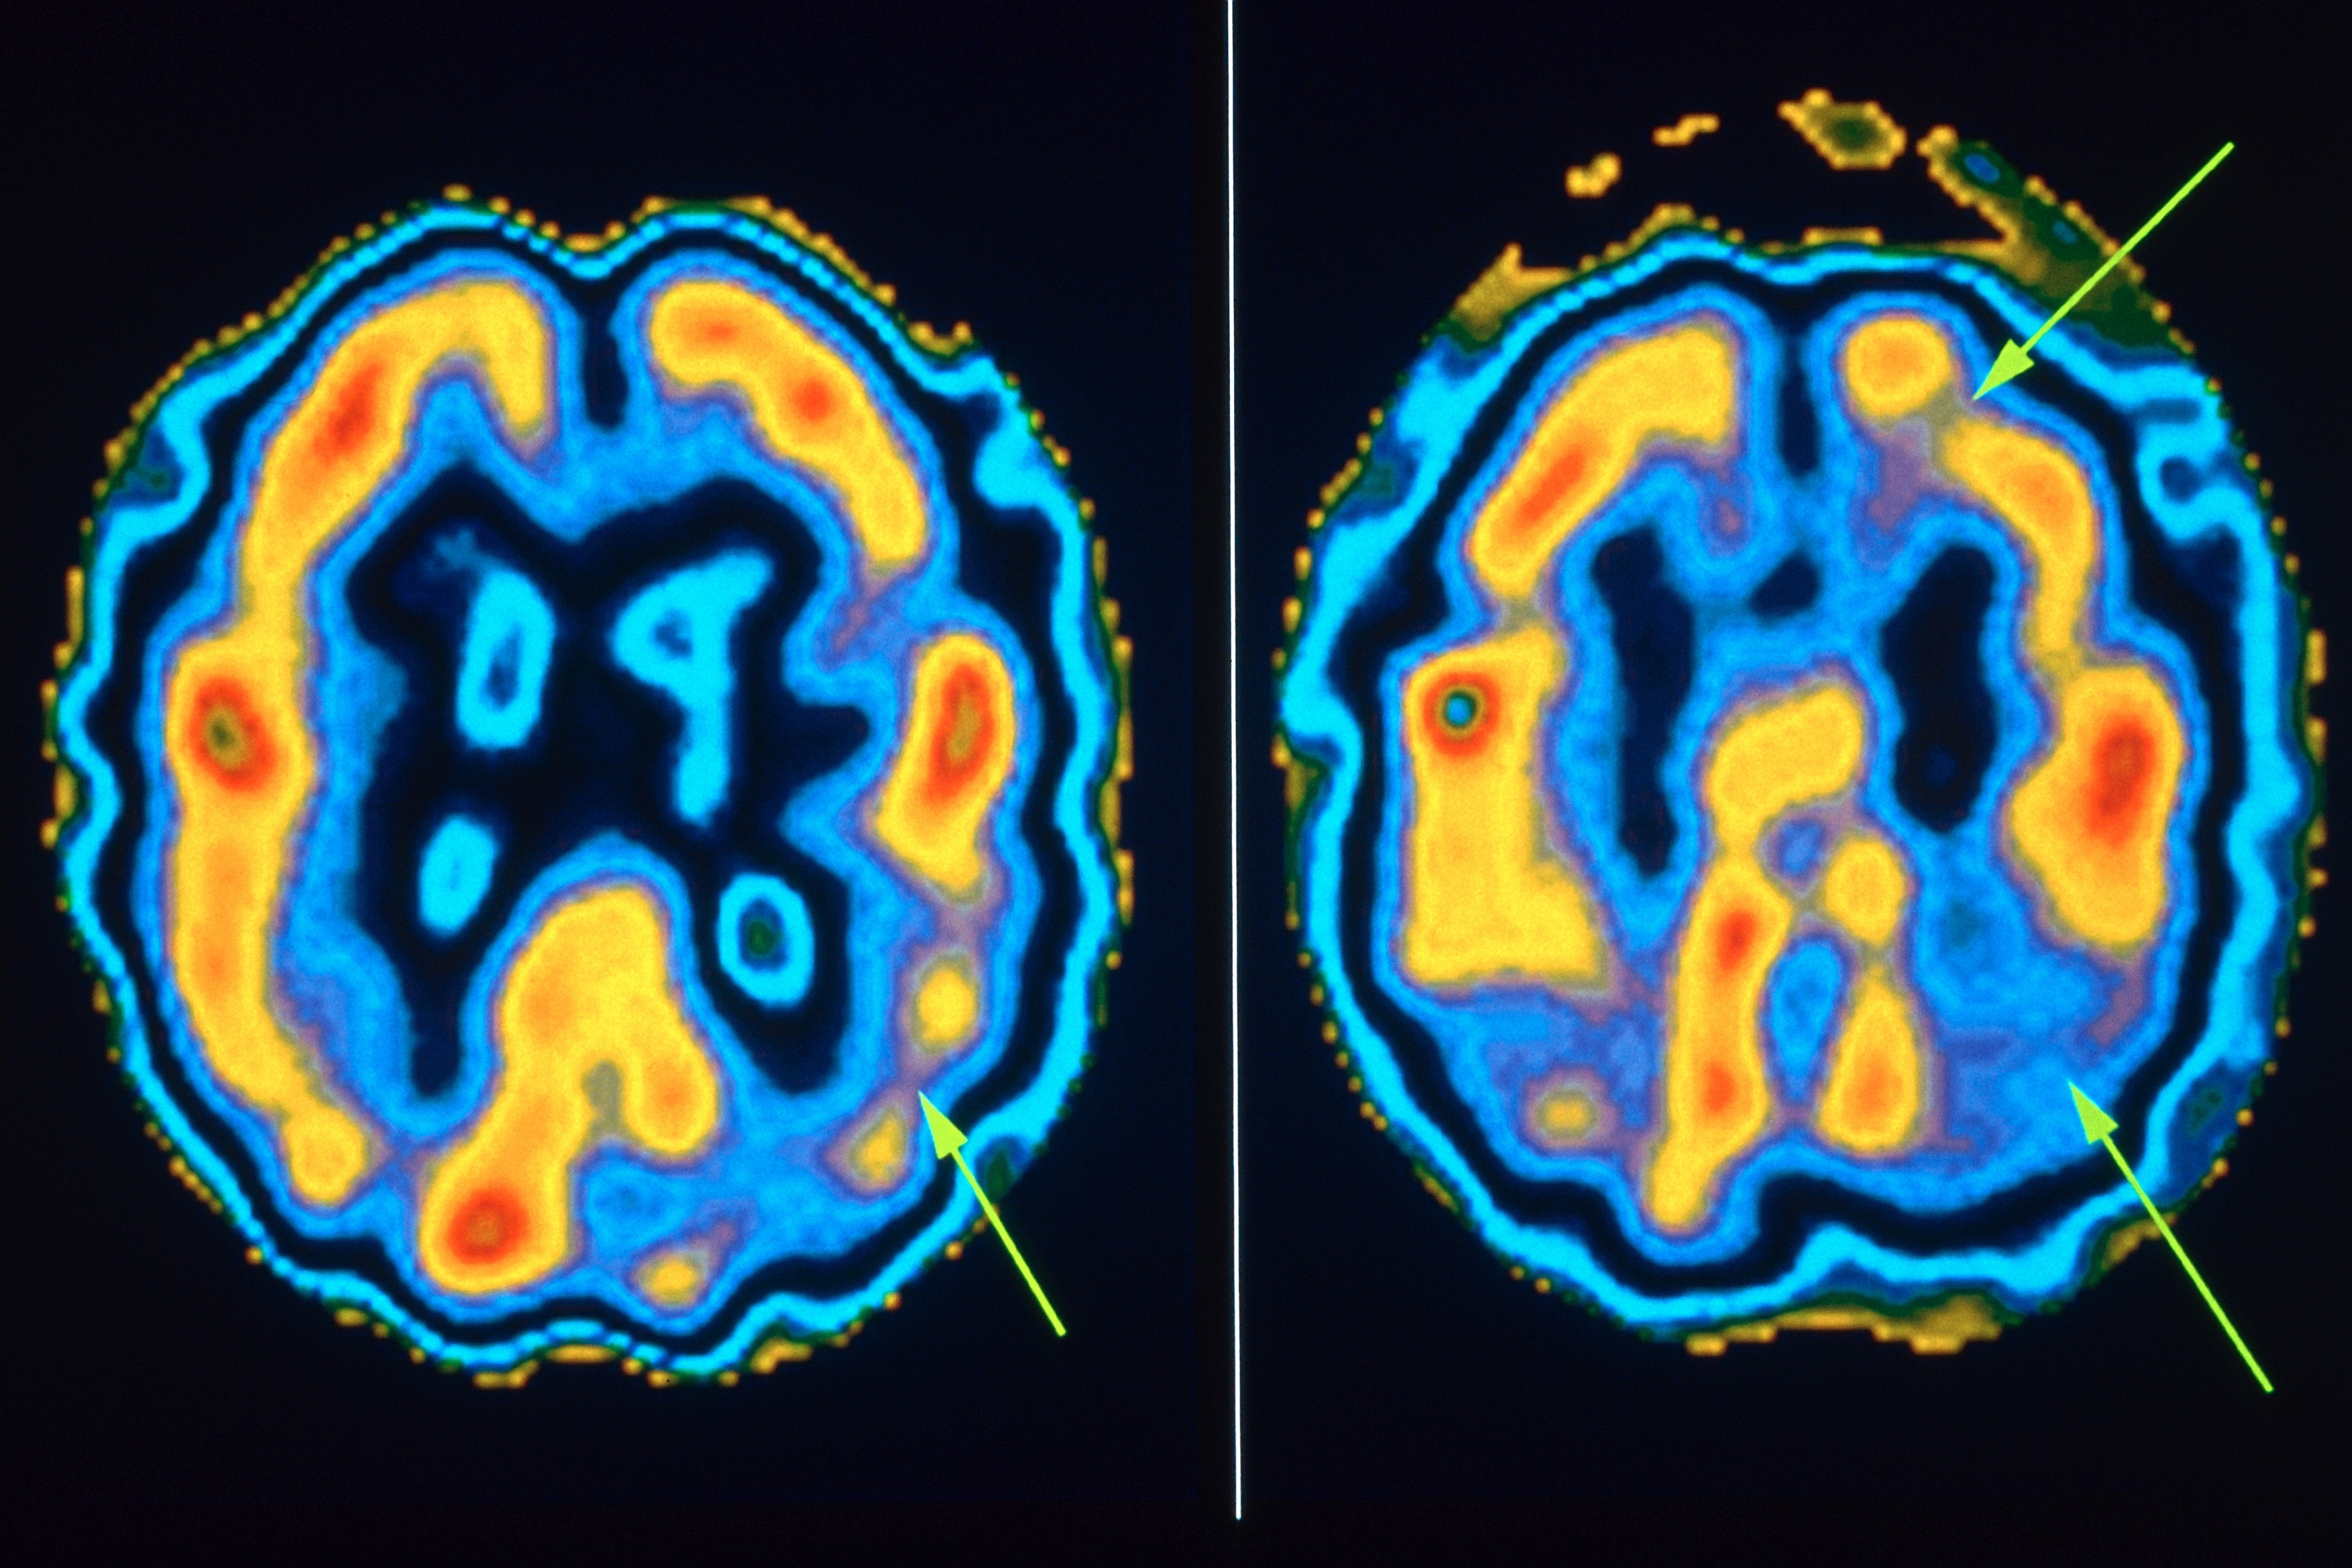

Moderní radiodiagnostika používá stále chytřejší přístroje, které už nekreslí jen tečky nebo čáry na papíře, ale při kombinaci s počítačovou tomografií nebo magnetickou rezonancí zobrazí umístění izotopu v konkrétním místě v těle. Barevné obrázky pak na podkladě získaných dat následně vygeneruje počítač.